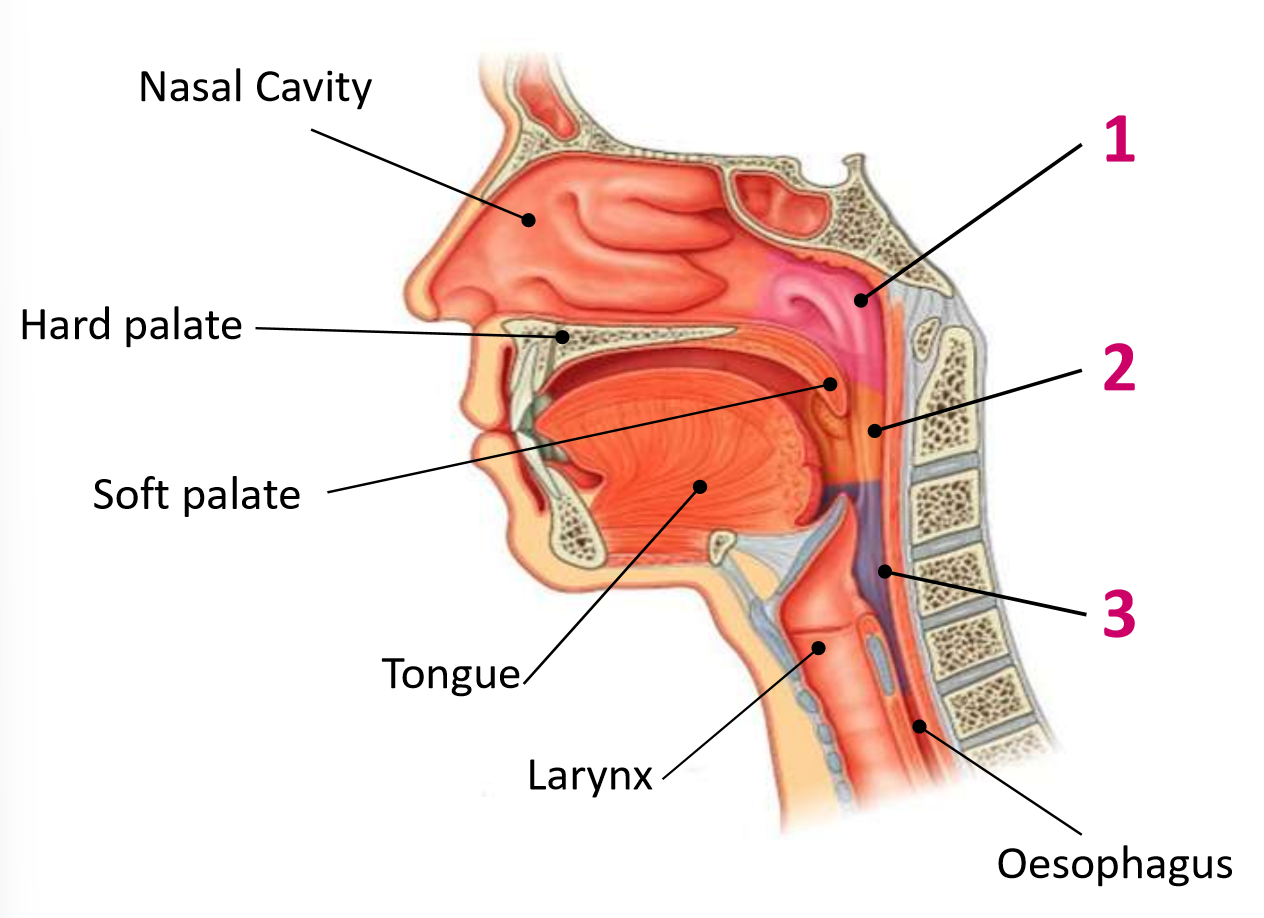

Which area of the head and neck do 1, 2, and 3 make?

pharynx

What region is 1?

nasopharynx

What region is 2?

oropharynx

What region is 3?

laryngopharynx

What is the anterior wall of 1?

posterior nasal choanae

What is the roof of 1?

body of sphenoid and basilar part of occipital

What is the posterior wall of 1?

anterior arch of atlas covered in pharyngobasilar fascia

What is the floor of 1?

soft palate

What is the anterior wall of 2?

oropharyngeal isthmus

What is the roof of 2?

soft palate

What is the floor of 2?

pharyngeal part of tongue and glossoepiglottic fold

What is the posterior wall of 2?

C2 and upper C3

What are the lateral walls of 2?

palatoglossal and palatopharyngeal arches